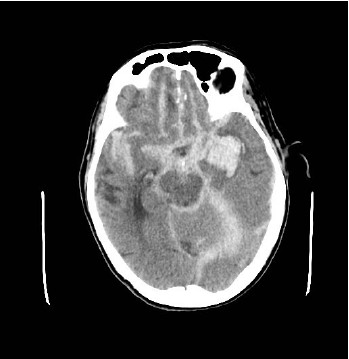

Paciente feminina, 55 anos de idade, tabagista há 25 anos com carga de 10 maços ano. Deu entrada no Grande Trauma com Glasgow 6, trazida pelo SAMU com relato de ter sido encontrada desacordada em casa pela vizinha. Realizada TC Crâneo (imagem 1):

Segundo o diagnóstico pela TC de Crâneo, as medidas a seguir fazem parte da prevenção da lesão neurológica secundária, exceto:

Ainda relativo à TAC de crânio do caso anterior, qual descrição abaixo caracteriza melhor a imagem no contexto do caso: